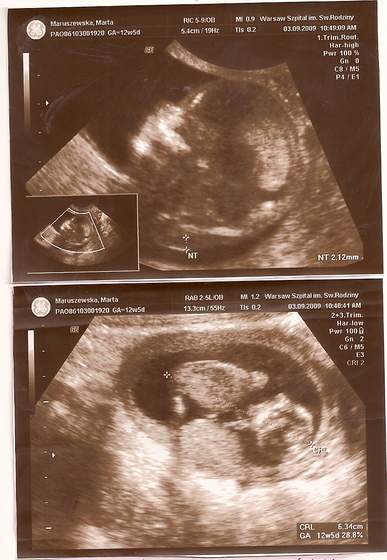

No to i ja się pochwalę naszą dzidzią ;-) ma 5.49cm, wczoraj robilismy badania prenatalne i wszystko jest super

![]()